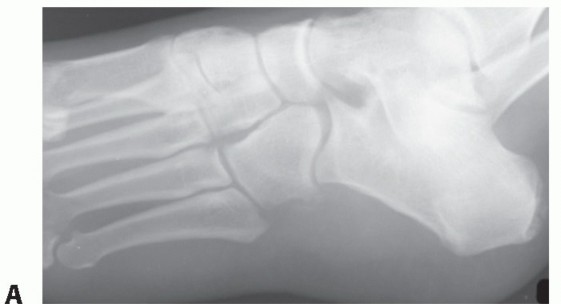

DEFINITION An accessory navicular is an osseous abnormality that is caused by a secondary ossification center…